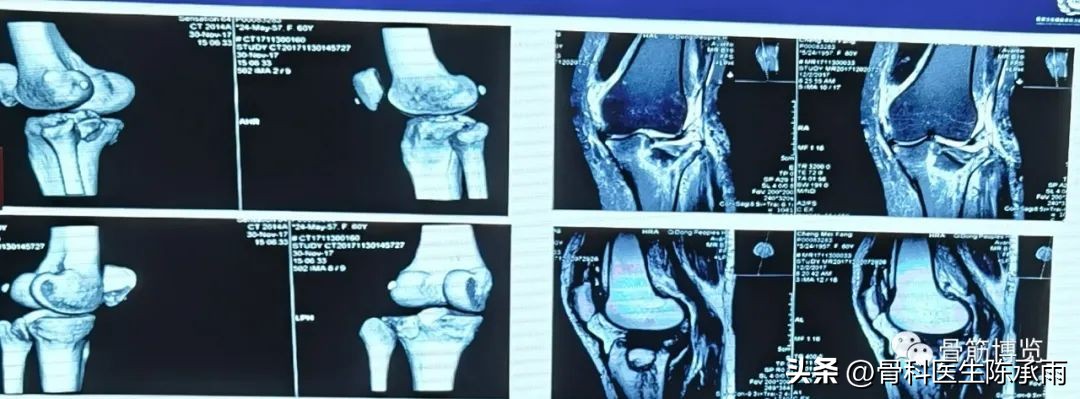

胫骨平台骨折的分型比较多,我们临床上常用的就是Schatzker分型和AO骨折的分型,还有骨折脱位的Hohi-Moore分型,这是我们常用的三个分型。

对AO 分型来讲,现在这是AO推出来更详细的,再分为ABC。随着分型的增加,从A到C骨折的损伤程度是越来越重,治疗也越来越困难,从1到2 ,123也是这个规律,骨折的分型就是给我们表明了骨折的一个损伤的程度,治疗办法和损伤的特点。我们对于骨折脱位的分型,常用Hohi-Moore分型,这个是弥补了,Schatzker和AO分型的一些缺陷。